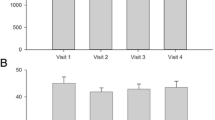

In all subjects the R2 response could be identified. Electrophysiological results of means are summarized in Table 1. Representative nBR responses are shown in Figure 1A. AUC was significantly decreased after smoking (Z df 29; p = 0.012), suggesting inhibition at brainstem level. Latency was unchanged before and after smoking. No correlation between smoking habits and electrophysiological results could be determined.

Representative nBR and PREP curves before an after smoking in a single subjects . NBR and PREP before smoking is shown in black. NBR and PREP after smoking is shown in red. (A) Area under the curve is decreased after smoking a cigarette suggesting an inhibition of trigeminal pain processing at brainstem level. (B) N2 and P2 latency are reduced after smoking a cigarette suggesting a facilitation of trigeminal pain processing at supraspinal level.

In 28 subjects PREP could be identified. Electrophysiological results of means are summarized in Table 2. Representative PREP responses are shown in Figure 1B. N2 latency (p = 0.002) and P2 latency (p = 0.022) were significantly reduced after smoking suggesting a facilitation at supraspinal level. Amplitudes were not significantly changed. No correlation between smoking habits and electrophysiological results could be determined.

In 28 subjects the R2 response could be identified. Electrophysiological results of means are summarized in Table 1. No significant changes regarding nBR latency and AUC were observed after caffeine consumption. No correlation between caffeine consumption and electrophysiological results could be determined.

In all subjects PREP could be identified. Electrophysiological results of means are summarized in Table 2. No significant changes regarding N2 latency, P2 latency, and PPA were observed after caffeine consumption. No correlation of caffeine consumption and electrophysiological results could be determined.